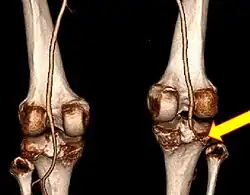

CT angiogram 3D reconstruction, posterior view showing a normal artery on the left, and occlusion to right popliteal artery as a result of a knee dislocation[11] -

If the ankle–brachial pressure index (ABI) is less than 0.9, CT angiography is recommended.[3] Standard angiography may also be used.[2] If the ABI is greater than 0.9 repeated physical exams over the next 24 hours to verify good blood flow may be sufficient.[2][9] The ABI is calculated by taking the systolic blood pressure at the ankle and dividing it by the systolic blood pressure in the arm.[2]